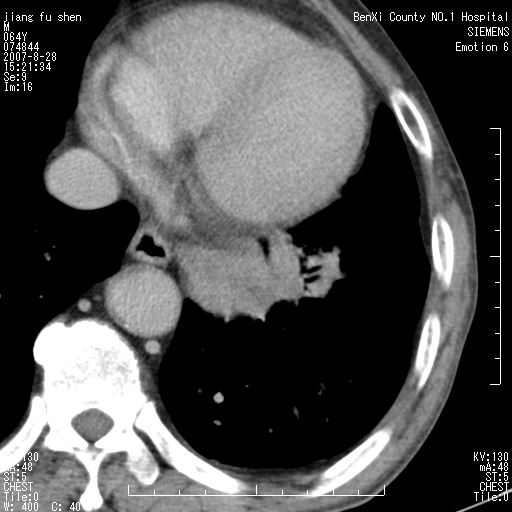

男、64、咳嗽、发烧一周、左肺呼吸音稍弱。既往肺结核,右手结核。

本次扫描患者未带原片,左肺下叶发现病灶。左肺上叶空洞,5组淋巴结肿大,1cm左右。

病灶边缘可见多量较长棘影及纤维条索状影,除外病灶边缘较光整,病灶有分叶表现,但多表现为较浅分叶,且向周围伸出之叶多呈尖角改变,且边缘较光整,病灶增强呈中度延时增强,且早期及中期仅轻度增强,结合患者病史,多考虑继发型肺结核,炎性增殖灶形成,不除外肺癌

左下叶支气管变窄,管腔光滑。软组织形状不规侧,分叶呈角形。结合病史考虑结核可能性大。肺癌不除。